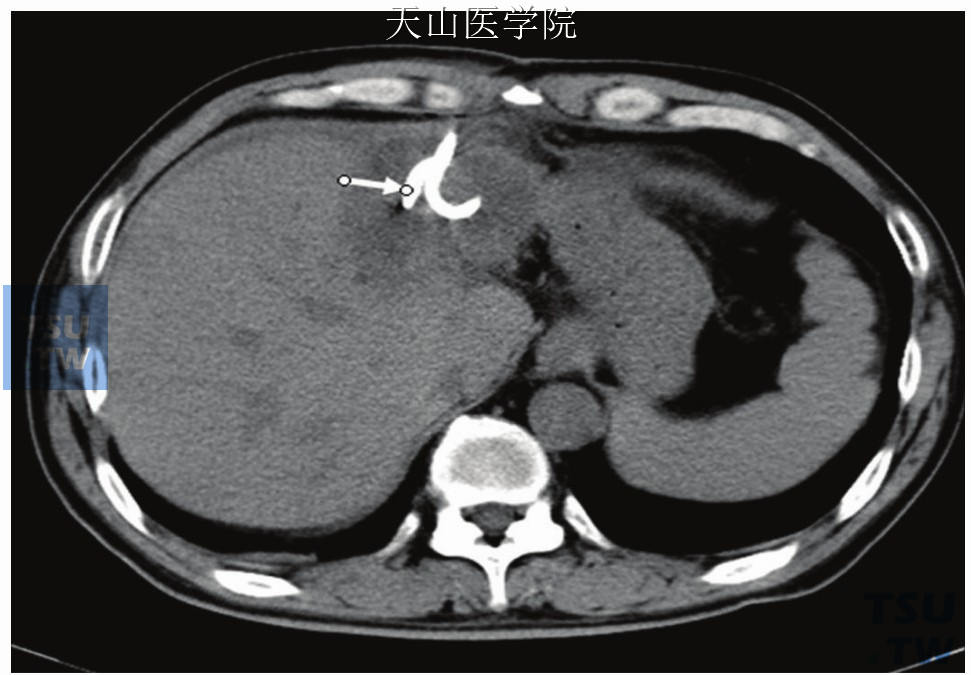

6手术指征与腹壁贴近、局限的单房腹腔脓肿。对较小脓肿(直径小于3cm)或多房性小脓肿不宜采用本手术。术前准备1.检查血常规、血小板和凝血功能。2.术前禁食8~12小时;腹胀明显者,可